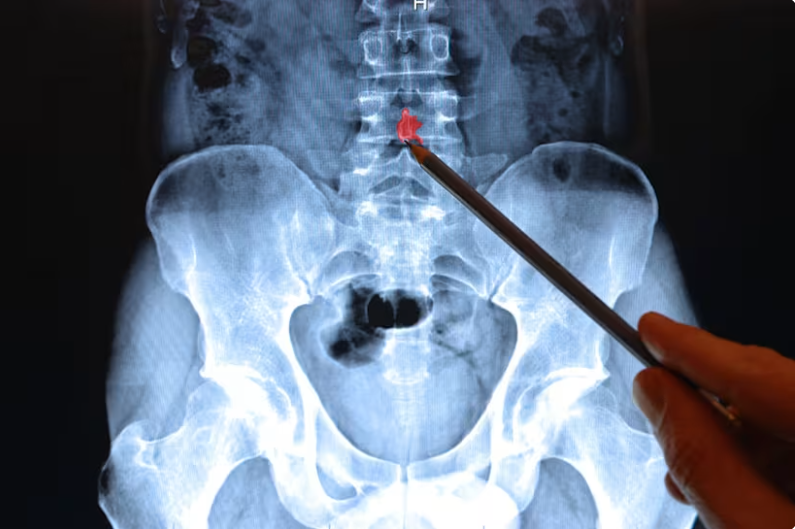

MRI for Lower Back Pain

MRI technology is genuinely remarkable. It gives clinicians a detailed, radiation-free window into the soft tissues of your spine — discs, nerves, and ligaments. But here's what most patients are never told: an MRI captures anatomy, not experience.

It shows what your spine looks like at rest, in a tube, on a particular Tuesday. It cannot show how your spine moves, which positions provoke your pain, which muscles have stopped firing correctly, or how your nervous system is interpreting signals from your body.

The result is a well-documented phenomenon in spine medicine sometimes called the "imaging-pain disconnect" — a consistent gap between what appears on a scan and what a patient actually feels.